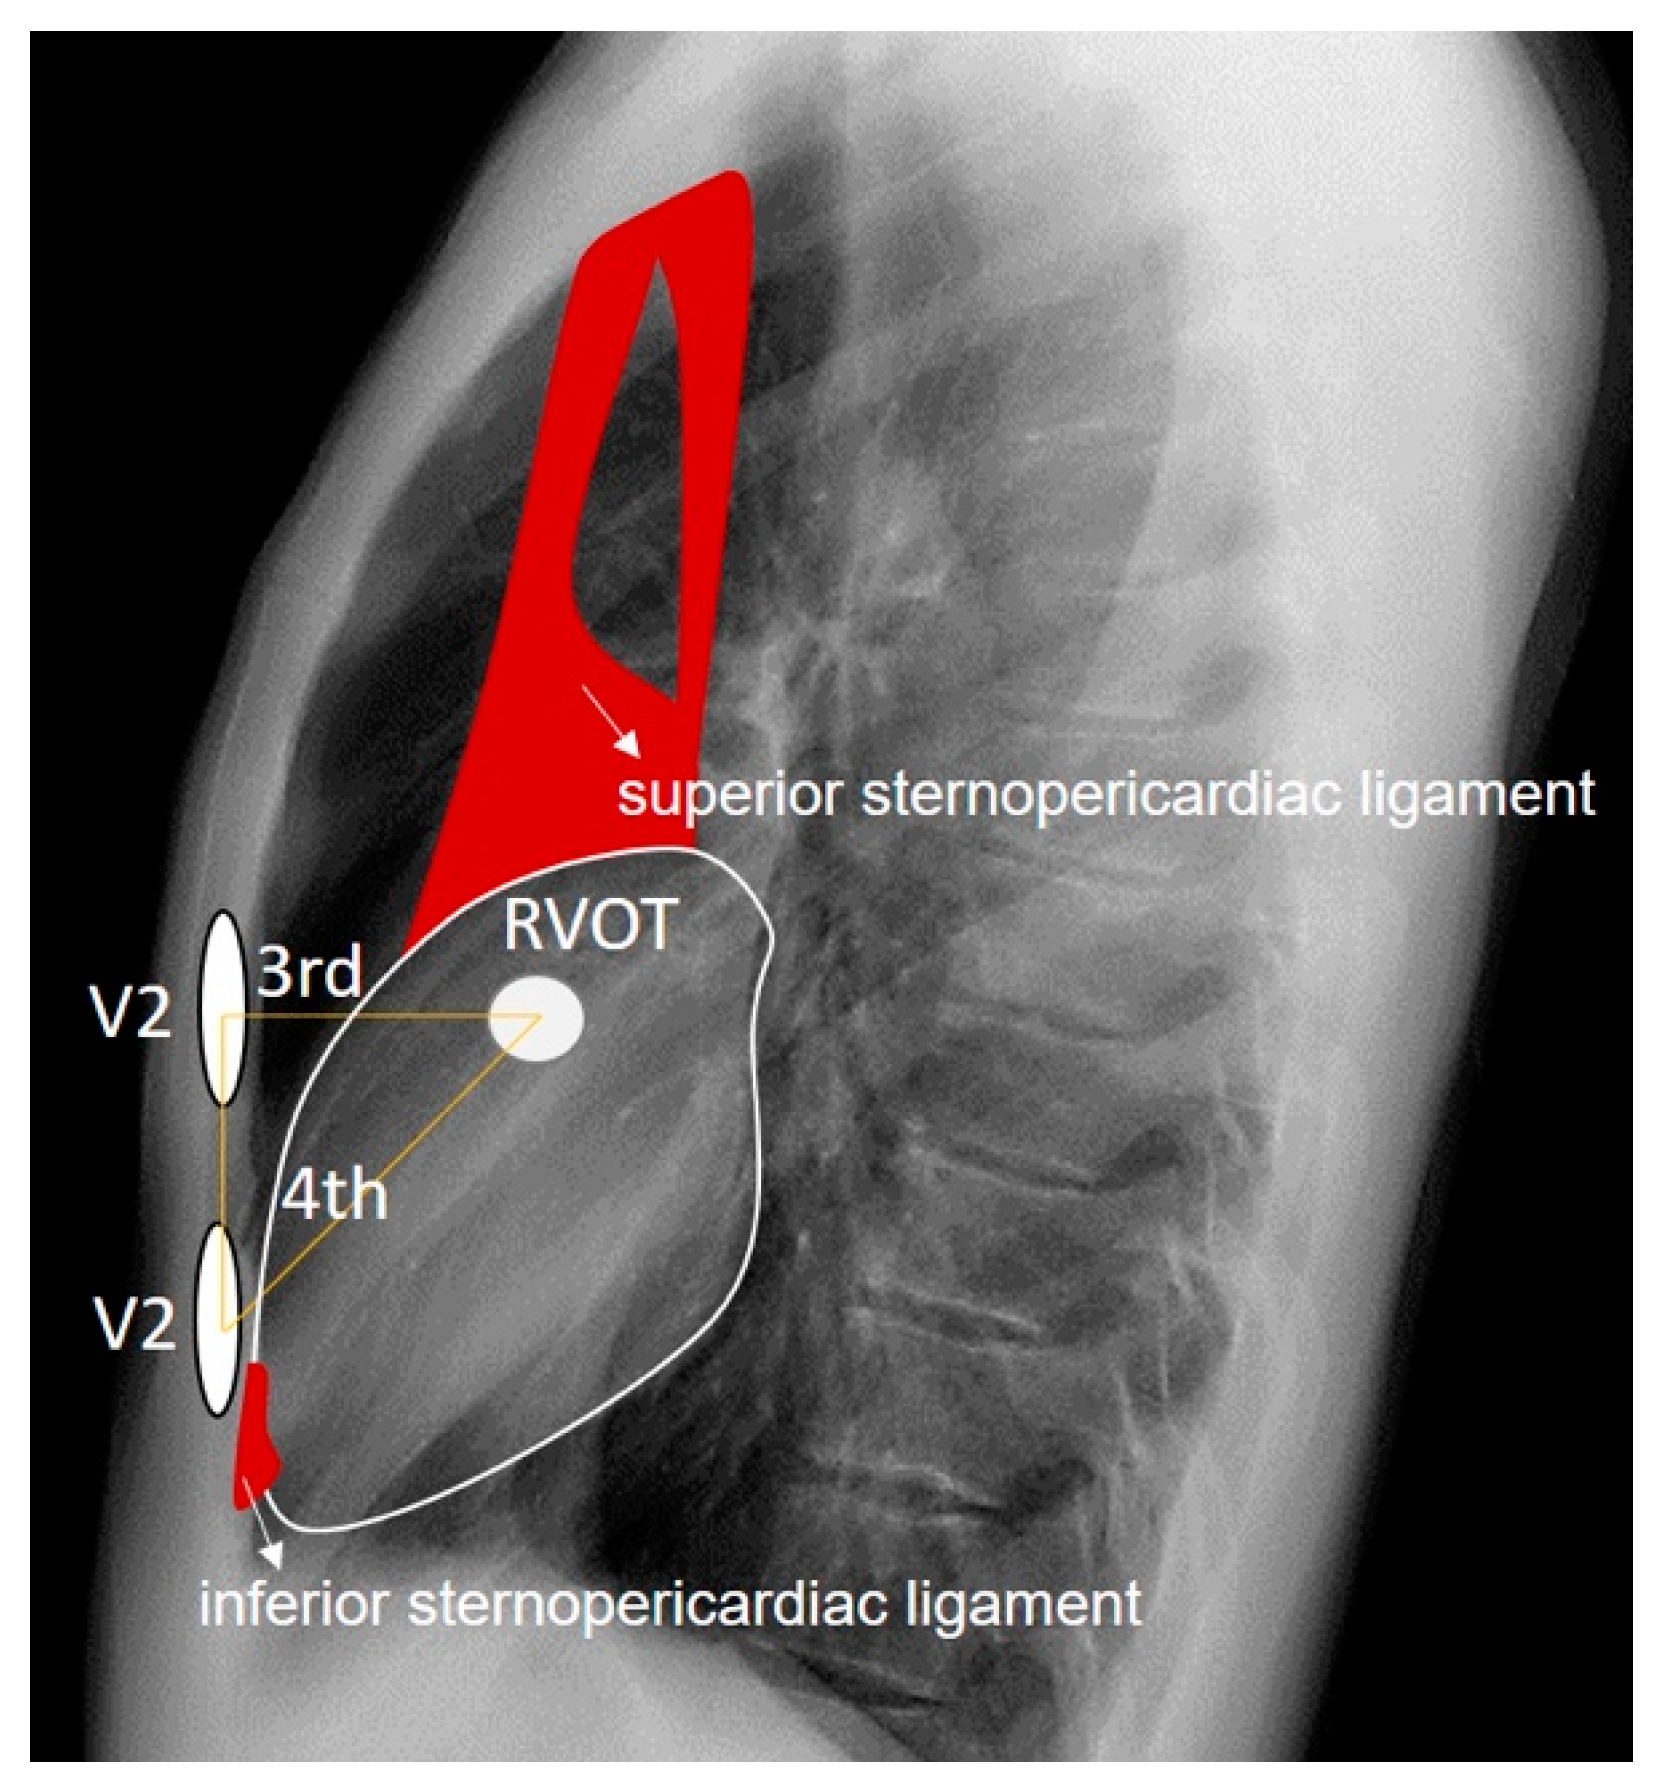

The RVOT is directly implicated in the emergence of Brugada patterns. Although in our patient it is located just behind the third intercostal space and directly behind lead V2 when placed in this space, type 2 Brugada patterns are better visualized with the V2 electrode positioned in the fourth intercostal space, where sternocardiac contiguity is present. This close relationship between the heart and the sternum at the sternocardiac junction is due to the presence of the inferior sternopericardial ligament, which promotes direct physical contact between the apical cardiac tissue and the sternum, as opposed to what happens in the tissue adjacent to the RVOT, where there is more air interposed. The inferior sternopericardial ligament contributes to maintaining the sternopericardial junction even in supine positions, which are typical for electrocardiogram recordings. Furthermore, in the supine position, the amount of retrosternal air in the third intercostal space may increase; this is not the case in the fourth intercostal space, where there is more tendency for direct sternocardiac attachment due to the mentioned ligament. This allows us to extend the anatomical reasoning applied in anteroposterior and lateral chest X-rays to the electrocardiographic analysis of leads. The superior sternopericardial ligament is longer and more “movable”. It generally extends from the cardiac base to the manubrium of the sternum, and for the purposes of our investigation, its presence is not significant (Figure 8).

Figure 8. We observe the approximate anatomical relationship of the RVOT concerning the V2 leads positioned at the third and fourth intercostal spaces. The superior and inferior sternopericardial ligaments are highlighted in red for emphasis. It is noteworthy that when V2 is placed at the fourth intercostal space, there is direct physical contact between V2 and the RVOT through denser tissues, contrasting with the more dielectric electrical conduction when V2 is positioned at the third intercostal space due to air interposition between V2 and the RVOT.